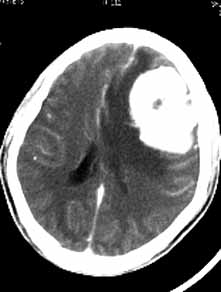

男性,36岁,头痛数年,近期伴有视蒙。

ct诊断:左额颞部脑膜瘤。